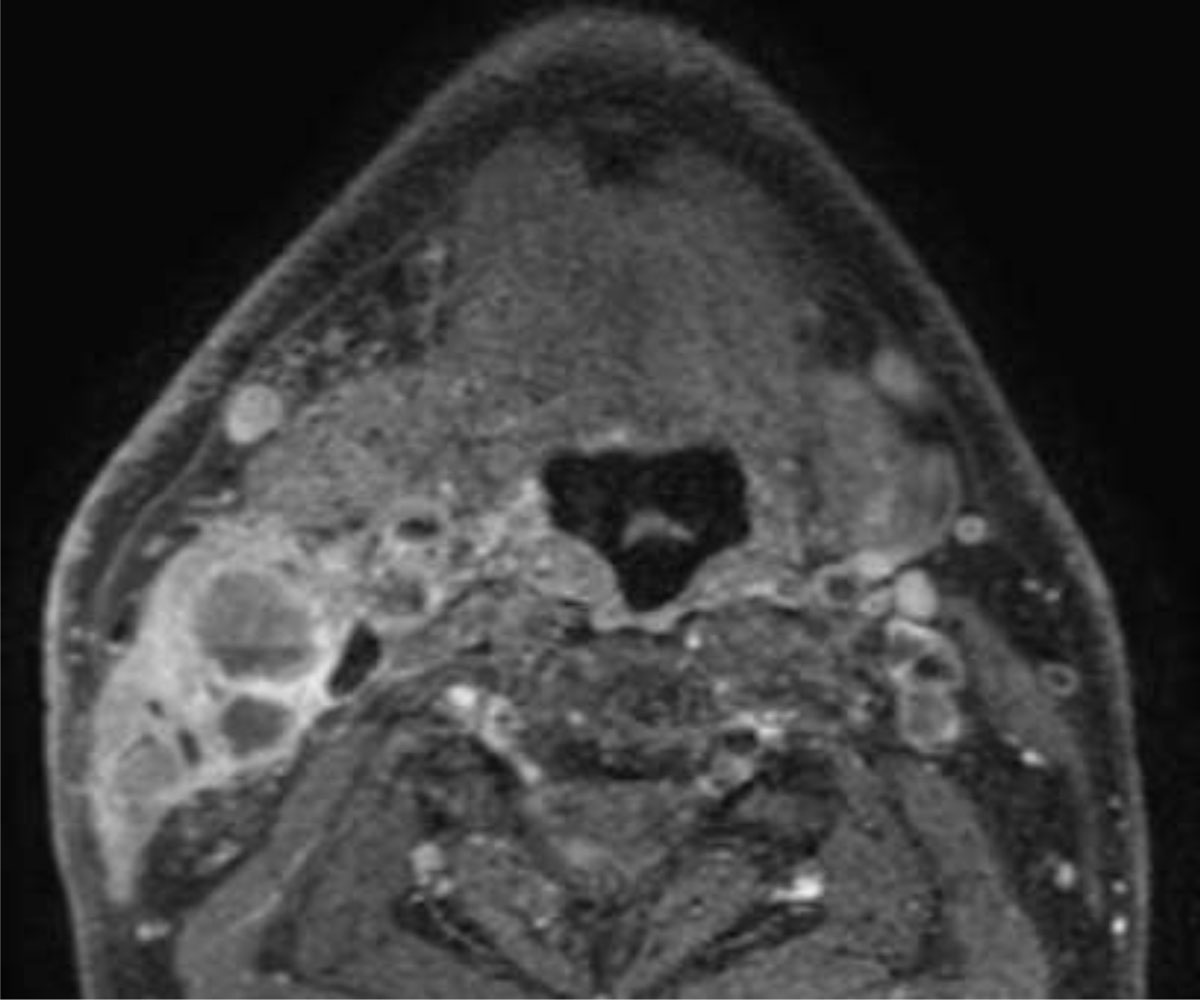

Figure 1

Patient with HPV-related oropharyngeal squamous cell carcinoma (not shown). Axial fat suppressed gadolinium enhanced MR section at the level of the tongue base shows predominantly cystic lymphadenopathy in the right neck (Level II).